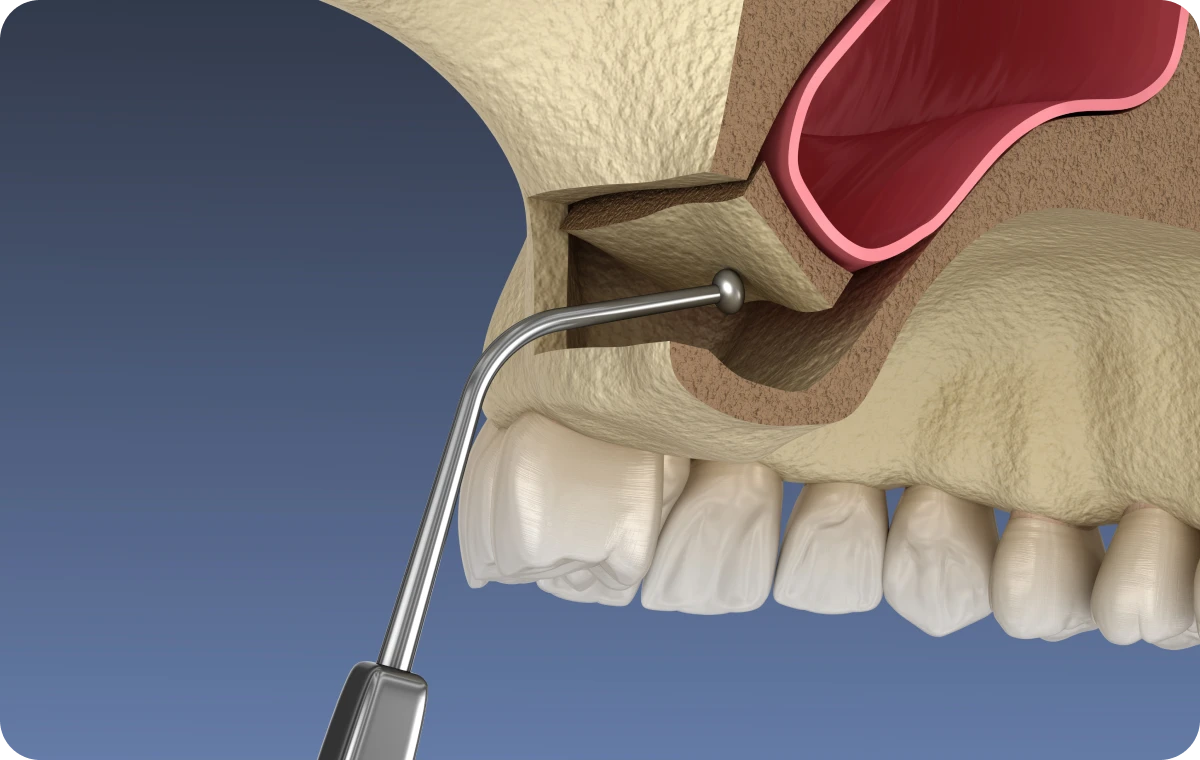

La chirurgie orale regroupe l’ensemble des interventions chirurgicales pratiquées au niveau de la bouche, des dents et des mâchoires. Elle peut inclure des extractions dentaires complexes (comme les dents de sagesse), la gestion de kystes ou de lésions buccales, ainsi que des chirurgies correctrices visant à améliorer la santé et la fonctionnalité de la sphère orale. Ces actes sont réalisés sous anesthésie locale, et dans certains cas sous anesthésie générale, afin d’assurer confort et sécurité aux patients.

- Un bloc opératoire pour anesthésie locale aux normes d’hygiène et d’asepsie en vigueur.